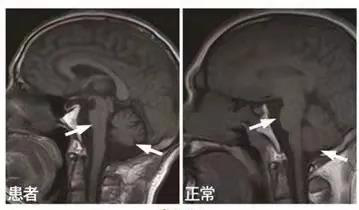

图 |核磁提示脑桥、小脑明显萎缩